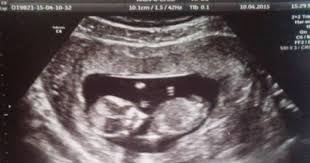

Bebegin Cinsiyeti Ne Zaman Belli Olur

Bebegin Cinsiyeti Ne Zaman Belli Olur from i4.hurimg.com

Hamilelik döneminde bebeğin cinsiyeti öğrenebilmek umudu ile anne adayına ultrason muayenesi yapılır. Anne baba olacağı öğrenen ebeveynler büyük bir sabırsızlıkla, heyecanla bebeklerinin kız mı yoksa erkek mi olacaklarını öğrenmek isterler. Merak edenler için araştırdık sorularınızın cevabını bulabileceğiniz bir video. Çünkü 12.haftada söylenen cinsiyette yüksek oranda hata payı olabilir. Bebeğin cinsiyeti ne zaman belli olur sorusunu kadın hastalıkları ve doğum uzmanı harika. Hamilelik sürecinin en heyecanlı anlarından biri bebeğin cinsiyetinin öğrenildiği zamandır. Bebeğin cinsiyeti ne zaman belli olur? Peki, ultrason ile görüntülenen bebeklerin cinsiyeti ne zaman belli olur?

Doğum heyecanı yaşayan her anne adayı bebeğin cinsiyetini merak eder. Bebeğin cinsiyeti ne zaman belli olur sorusunu kadın hastalıkları ve doğum uzmanı harika. Tüm bu durumlara karşın bebeğin cinsiyetini kesin olarak ne zaman öğrenebilirim diye sorarsanız 16.haftada net olarak anlaşılabilir. Hamilelik döneminde bebeğin cinsiyeti öğrenebilmek umudu ile anne adayına ultrason muayenesi yapılır. Watch & download video bebeğin cinsiyeti ne zaman belli olur.